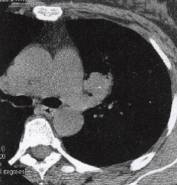

肝癌肺转移(3)肺部其他恶性肿瘤如肺原发肉瘤、肺癌肉瘤等。常症状轻微甚至无症状就诊时间 较晚,X线及CT表现为圆形、椭圆形肿块,边缘光滑,分叶多不明显,可为小切迹样或铸 型表现,直径多达6〜7cm,大者可占据一叶肺甚至一侧胸腔(图4)。增强肿块呈不规则

明显强化,表面常有包膜或假包膜。极少有肺门纵隔淋巴结转移。 医学百科网 | YxBaike.Com